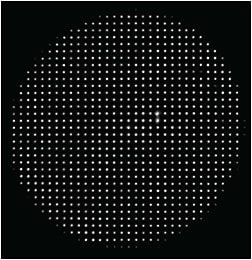

High-resolution Aberrometer

HIGH-RESOLUTION SENSOR MAXIMIZES CAPTURE RATES

- High-resolution Hartmann-Shack wavefront sensor (5 x higher than previous generation)

- Fourier reconstruction algorithms using up to 1257 micro-refractions over a 7-mm wavefront

- Improved accuracy and ability to measure complex wavefronts and highly aberrated eyes

INCREASED RESOLUTION PROVIDES

- Ability to capture images of more eyes

- Improved spot quality, reduces spot crossover effect

- Detection of HOAs

- Better reconstruction